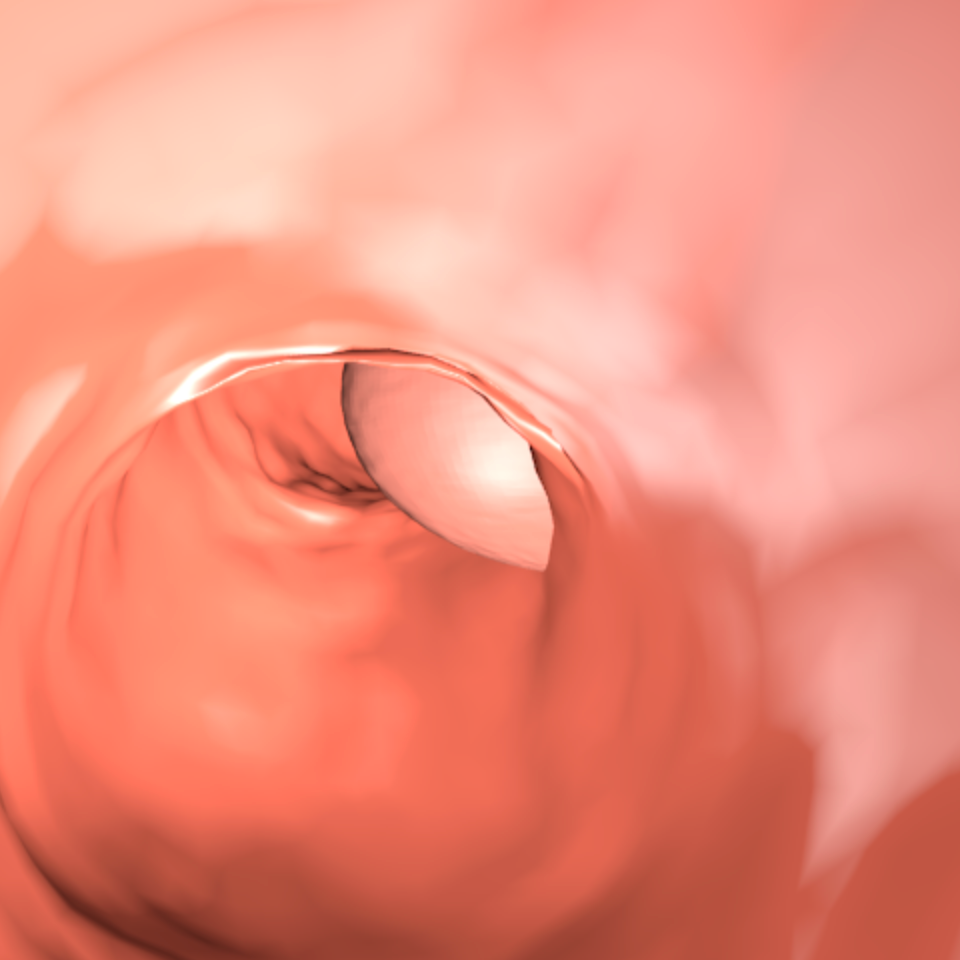

Our 3D colons structure is a cone composed by 2454 faces. Vertices are randomly displaced following a normal distribution in order to simulate the tissues in the colon. Additionally, the colon structure is modified by displacing 7 segments as in Figure 3. For the textures we used a base color [0.80, 0.13, 0.18] (RGB). For each sample we shift the color to other tones of brown, orange and pink. One single polyp is used on every image, which is placed inside the colon. It can be either in the colon’s walls or in the middle. Polyps are distorted spheres with 16384 faces. Samples with polyps occupying less than 20,000 pixels are removed.

Lighting is composed by a white ambient light, two white dynamic lights that project glare into the walls, and three negative lights that project black light at the end of the colon. We found that having a dark area at the end helps CycleGAN to understand the structure of the colon. The 3D scene must be similar to real colon images because otherwise, the CycleGAN will not translate properly the images to the real-world domain. Figure 4 illustrates the images and ground truth generated by the 3D engine.

4 Synth-Colon

We publicly release Synth-Colon, a synthetic dataset for polyp segmentation. It is the first dataset generated using zero annotations from medical professionals. The dataset is composed of 20 000 images with a resolution of 500500. Synth-Colon additionally includes realistic colon images generated with our CycleGAN and the Kvasir training set images. Synth-Colon can also be used for the colon depth estimation task [12] because we provide depth and 3D information for each image. Figure 1 shows some examples from the dataset. In summary, Synth-Colon includes: